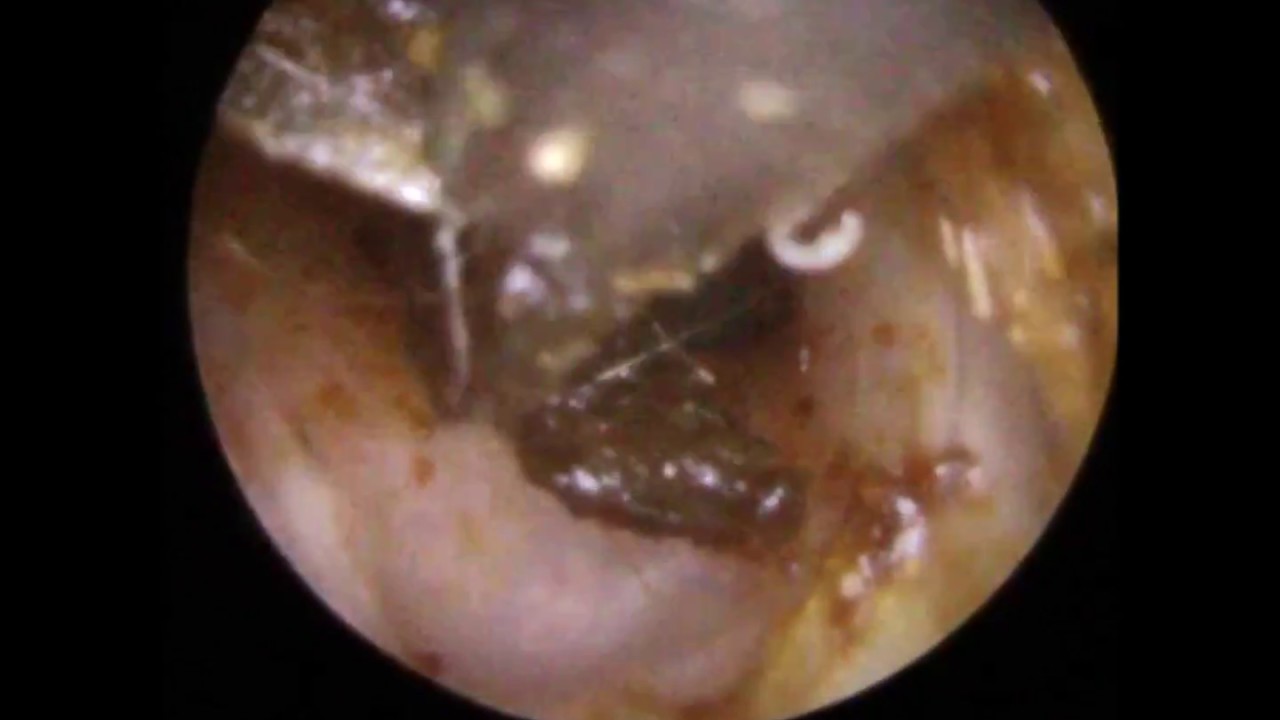

Removing Sticky Ear Wax From Ear Canal & Drum - Mr Neel Raithatha (The Hear Clinic) - YouTube

Next is a video clip concerning Removing Sticky Ear Wax From Ear Canal & Drum - Mr Neel Raithatha (The Hear Clinic) - YouTube which is currently trending and is being looked for by numerous netizens, you can play it straight on this page for ideas or maybe download and install videos to be utilized as video collections on your device.